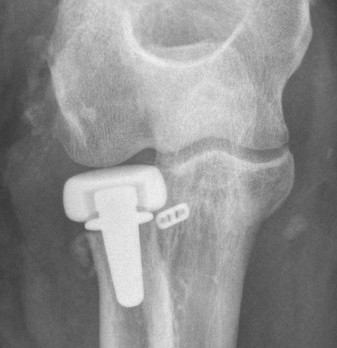

Radial head replacement with lag screw fixation of Type II coronoid

Radial head replacement with lasso fixation of small coronoid fragment

1. Restore coronoid stability - ORIF type II / III, suture repair type I

2. Restore radial head stability - radial head ORIF or arthroplasty

3. Restore lateral stability - LCL repair and common extensor origin +/- reconstruct +/- internal brace

4. +/- Restore medial stability - repair MCL if residual stability